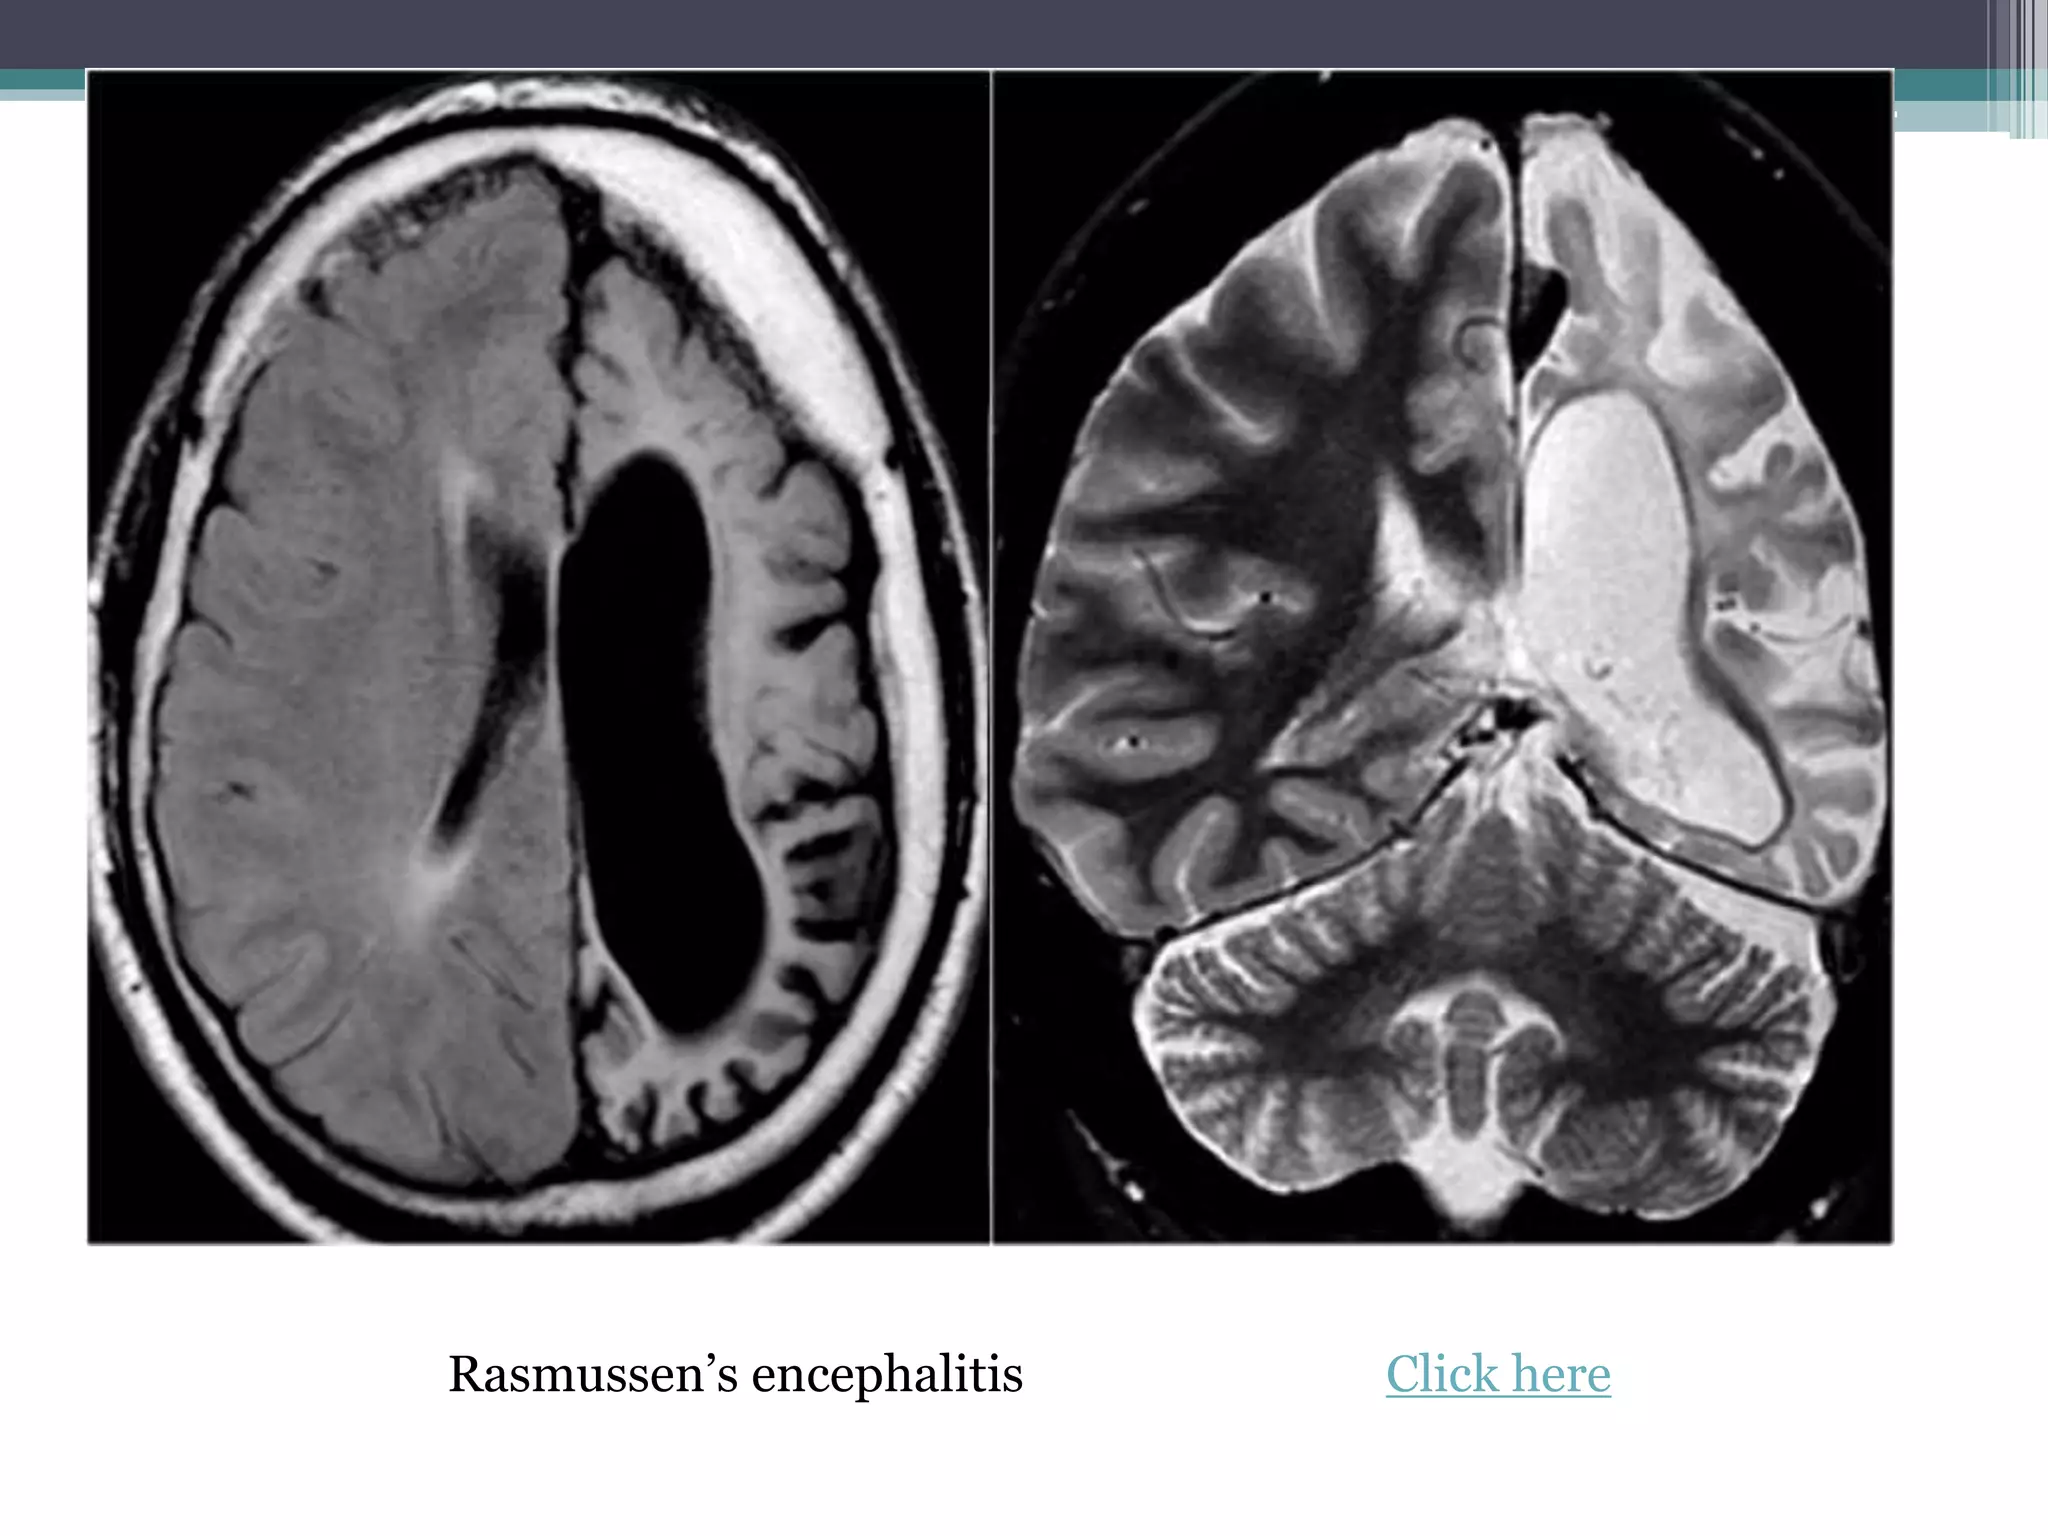

7. Rasmussen’s encephalitis • Progressive hemiatrophy of the

cerebral hemisphere due to unknown

etiology

• Intractable seizures

• Ipsilateral ventricular enlargement

• Click here

Rasmussen’s encephalitis Click here